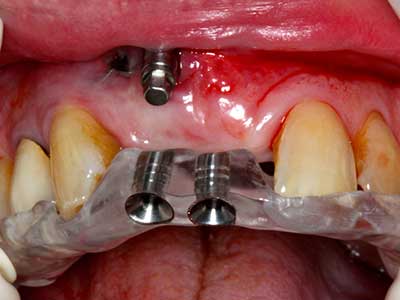

Fig. 14: Placement of four tapered RSX implants (Bego Implant Systems, Bremen).

Fig. 15: The one-year follow-up x-ray examination shows stable conditions at the bone level.

Fig. 16: The intraoral conditions are also stable with embedding of the implants in keratinized gingiva.

Fig. 23: Final mobilization of the palatally branched distraction segment with the chisel.

Fig. 24: Application of the distractor (TRACK-System, KLS Martin).